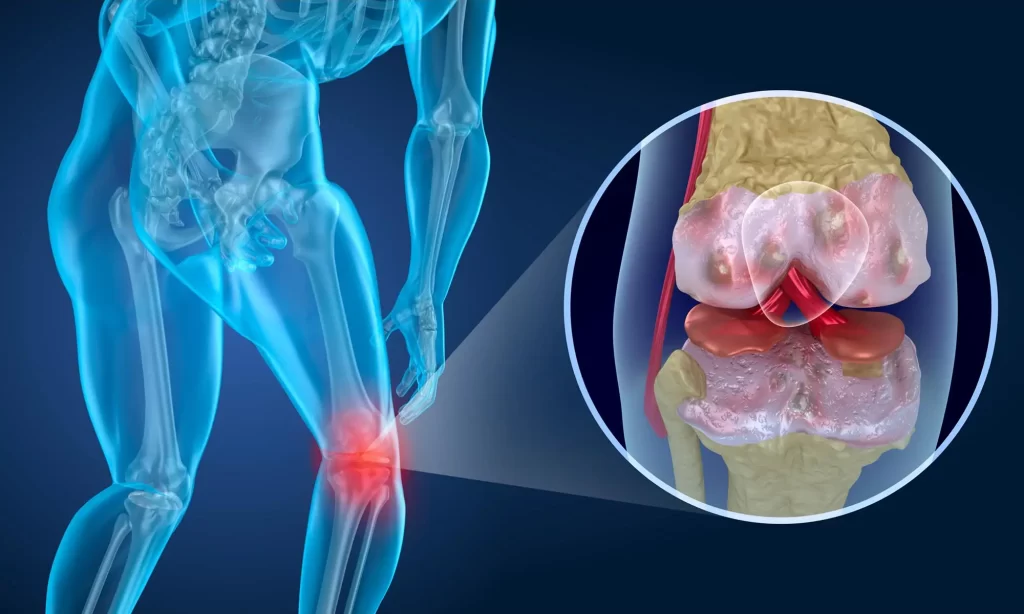

Knee pain affects more than 25% of adults worldwide and can affect people of any age. While physical therapy and prescription medications can effectively treat mild pain, those suffering from severe pain may require surgery.

Stem cell therapy may be an option for patients struggling to manage knee pain but who want to postpone knee replacement surgery. Renew Medical Centre wants to help patients understand stem cell treatment, its uses and limitations, and how it may help some find relief from knee pain caused by injury or arthritis.

A doctor will take stem cell samples from other parts of your body and reimplant them into an injured area during treatment. For knee pain, this could entail extracting bone marrow or fat tissue cells and injecting them into knee joints.